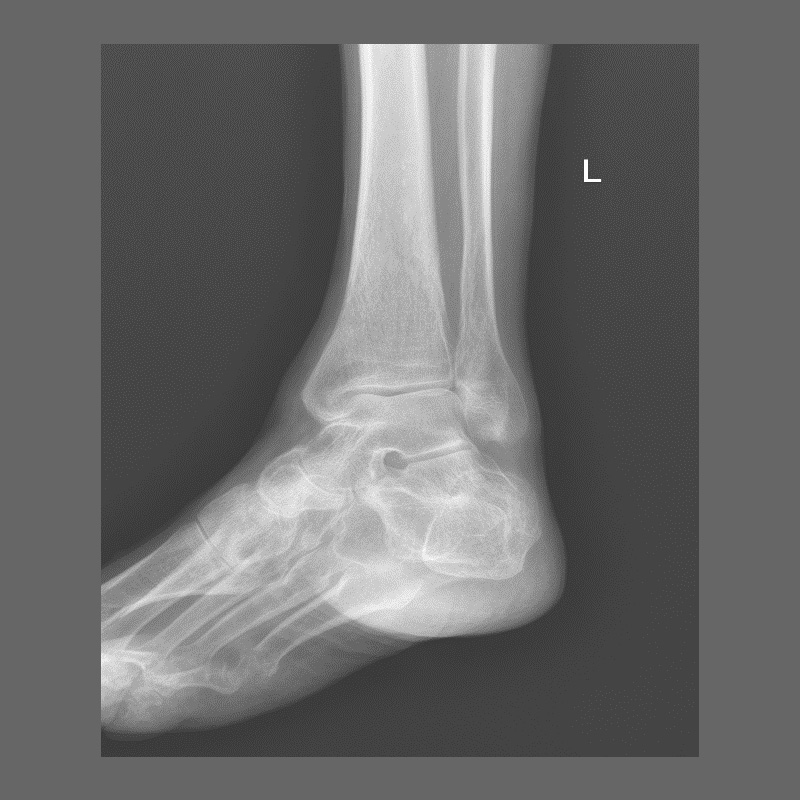

КЛІНІЧНА ГАЛЕРЕЯ GENÈVE 40M: